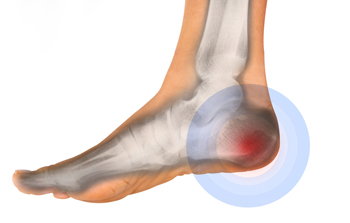

The Many Types of Heel Pain

The heels of the feet endure a great deal of stress and, therefore, are often open to pain and injury. The most common causes of heel pain are plantar fasciitis, Achilles tendonitis, bone spurs, and stress fractures. Heel bursitis, Sever’s disease, and Haglund’s syndrome are other causes that occur less frequently. Pain can be experienced behind the heel, within the bone itself, and under the heel. Simply stepping on a hard rock can cause pain under the heel, but the most common cause is plantar fasciitis. This is an overuse injury to the tissue that runs under the foot and connects the heel to the toes. Chronic plantar fasciitis can also lead to the development of heel spurs on the calcaneus, the main heel bone. Inflammation to the Achilles tendon from overuse is the most frequent cause of pain behind the heel. A podiatrist, a medical doctor who is trained in ailments of the feet and ankles, can diagnose the cause of heel pain by conducting a number of tests. These may include X-rays and electronic imaging tests. If you are suffering from heel pain and are unsure of the cause, it is suggested that you make an appointment with a podiatrist today.

Causes of Heel Pain

Heel pain is often associated with plantar fasciitis. The plantar fascia is a band of tissues that extends along the bottom of the foot. A rip or tear in this ligament can cause inflammation of the tissue.

Achilles tendonitis is another cause of heel pain. Inflammation of the Achilles tendon will cause pain from fractures and muscle tearing. Lack of flexibility is also another symptom.

Heel spurs are another cause of pain. When the tissues of the plantar fascia undergo a great deal of stress, it can lead to ligament separation from the heel bone, causing heel spurs.

Heel Pain

Heel pain can be difficult to deal with, especially if you do not know what the underlying cause is. If you ignore your heel pain, the pain can magnify and potentially develop into a chronic condition. Depending on the location of your heel pain, you have developed a specific condition.

One condition is plantar fasciitis. Plantar fasciitis is caused by the inflammation of the plantar fascia, or the band of tissue that connects the heel bone to the base of the toes. The pain from this condition is initially mild but can intensify as more steps are taken when you wake up in the morning. To treat this condition, medication will likely be necessary. Plantar fasciitis is often associated with heel spurs; both require rest and special stretching exercises.

There are various options your podiatrist may suggest for heel pain. Treatment options for heel pain typically include non-steroidal anti-inflammatory drugs (NSAIDS), which may reduce swelling and pain. Other options are physical therapy, athletic taping, and orthotics. In severe cases of heel pain, surgery may be required.

Preventing heel pain is possible. If you are looking to prevent heel pain from developing in the future, be sure to wear shoes that fit you properly and do not have worn down heels or soles. Be sure to warm up properly before participating in strenuous activities or sports that place a lot of a stress on the heels. If you are experiencing any form of heel pain, speak with your podiatrist to determine the underlying cause and receive the treatment you need.